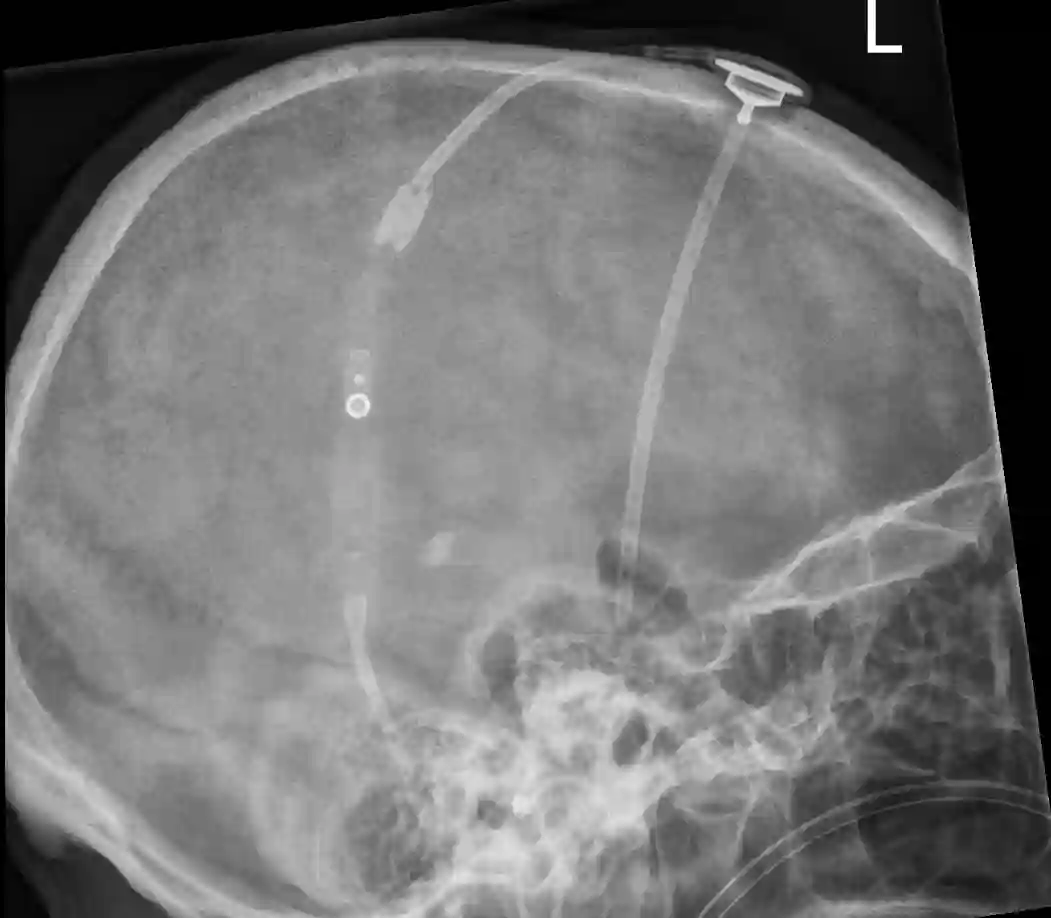

Das verlässliche Auslesen der aktuell eingestellten Druckstufe der Codman Hakim Shuntventile kann über eine Röntgenaufnahme des Shuntventils erfolgen.

Bildgebung